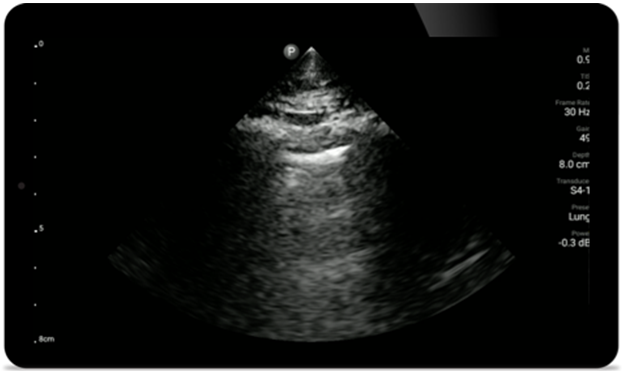

As soluções do Lumify para POC podem ajudar você a detectar o tubo endotraqueal na traqueia, auxiliar em procedimentos de cricotireotomia, diagnosticar derrame pleural e doenças alveolares intersticiais.